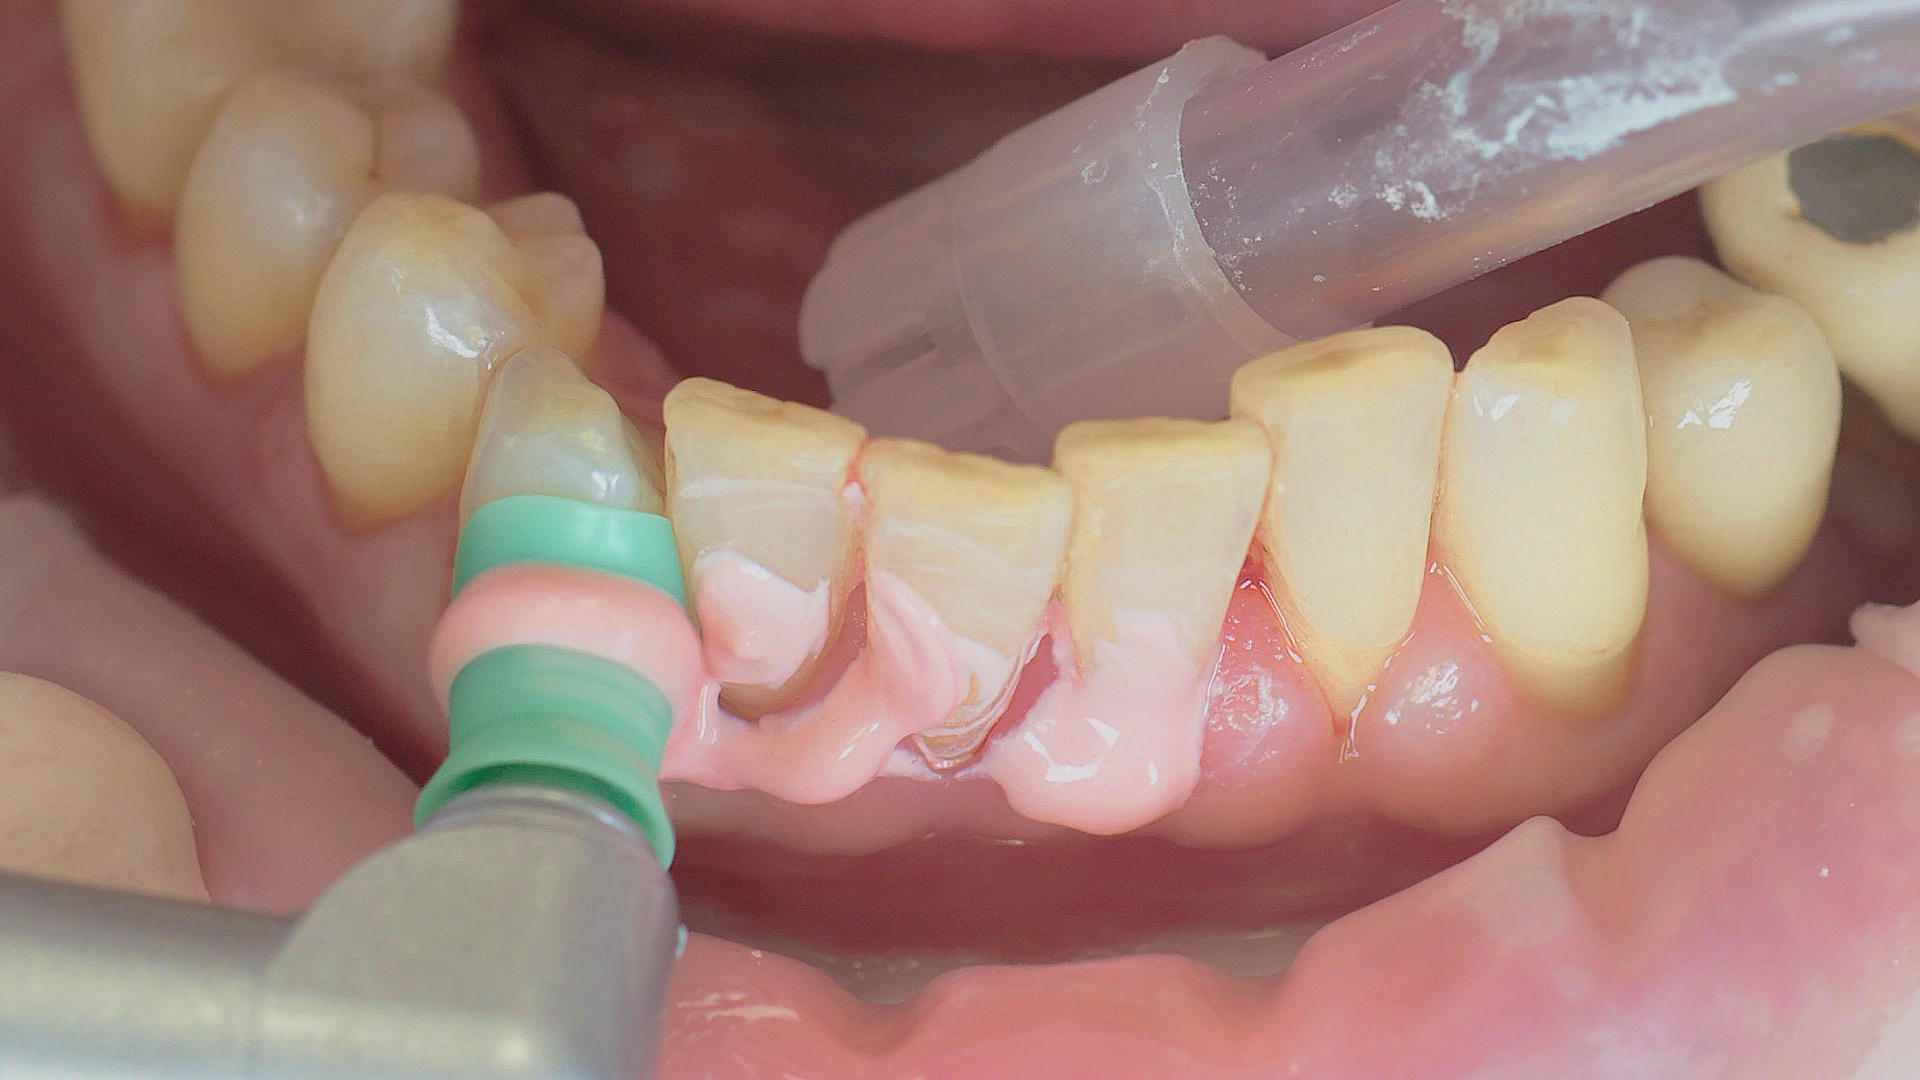

Every dental examination is based on a detailed medical history combined with targeted diagnostics con- taining as much detail as possible: The dentist records systemic risk factors such as diabetes or smoking and identifies any potential increased tendency to inflammation.[3] Hard and soft tissues are examined and periodontal pockets are probed in a screening test according to PSR (Periodontal Screening and Recording). In case of abnormal findings, the periodontal status is then re- corded and therapy is initiated where necessary. This treatment begins with professional biofilm management, by using, for example, rotary cups and polishing com pounds (Fig. 1), and comprehensive instructions in oral hygiene. Sonic or ultrasonic systems remain an effective alternative or supplement to manual instruments for sub- gingival debridement and biofilm management (presentation by Prof. Dr Ulrich Schlagenhauf; Fig. 2). Supplementary use of photodynamic therapy, air polishing or local and systemic antibiotics is not adequately documented (Prof. Dr Sema Hakki).[4] According to Dr Sergio Bizzarro, improved biomarker diagnostics may lead to an increase in customised patient therapy in the future.

An air scaler efficiently performs the initial debridement

Fig. 2: An air scaler efficiently performs the initial debridement, as part of initial periodontal therapy.